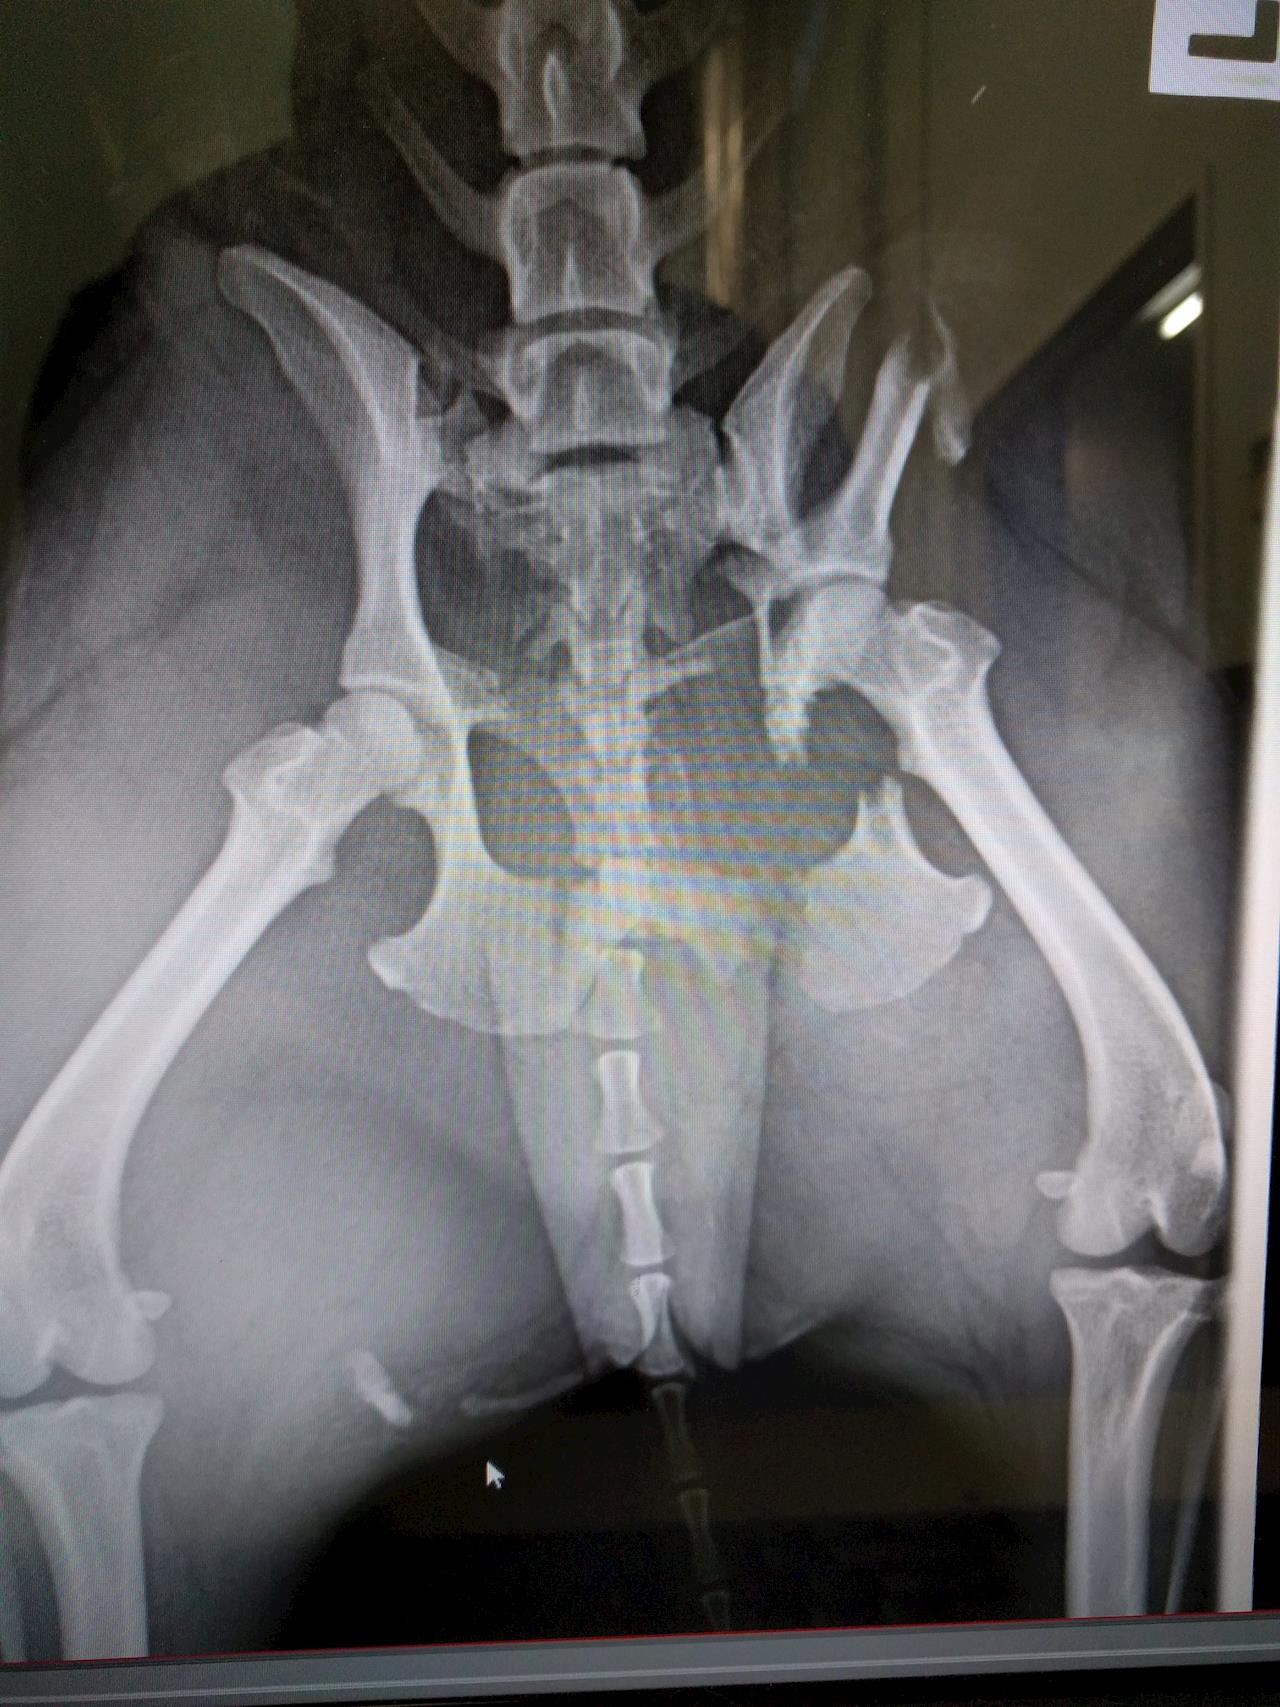

Pepper the Pug - Fractured Pelvis

There's quite a few fractures, mostly to the right hand part of her pelvis. She'll most likely need a plate to repair this side. One of the fractures is very close to her hip joint which could pose issues but it's hard to tell from the x-ray. She also has a fracture where the pelvis attaches to the sacrum on her left side which will probably need to be pinned. Her spine and tail appear to be fine and she moved her damaged leg and tail slightly when we visited this morning.